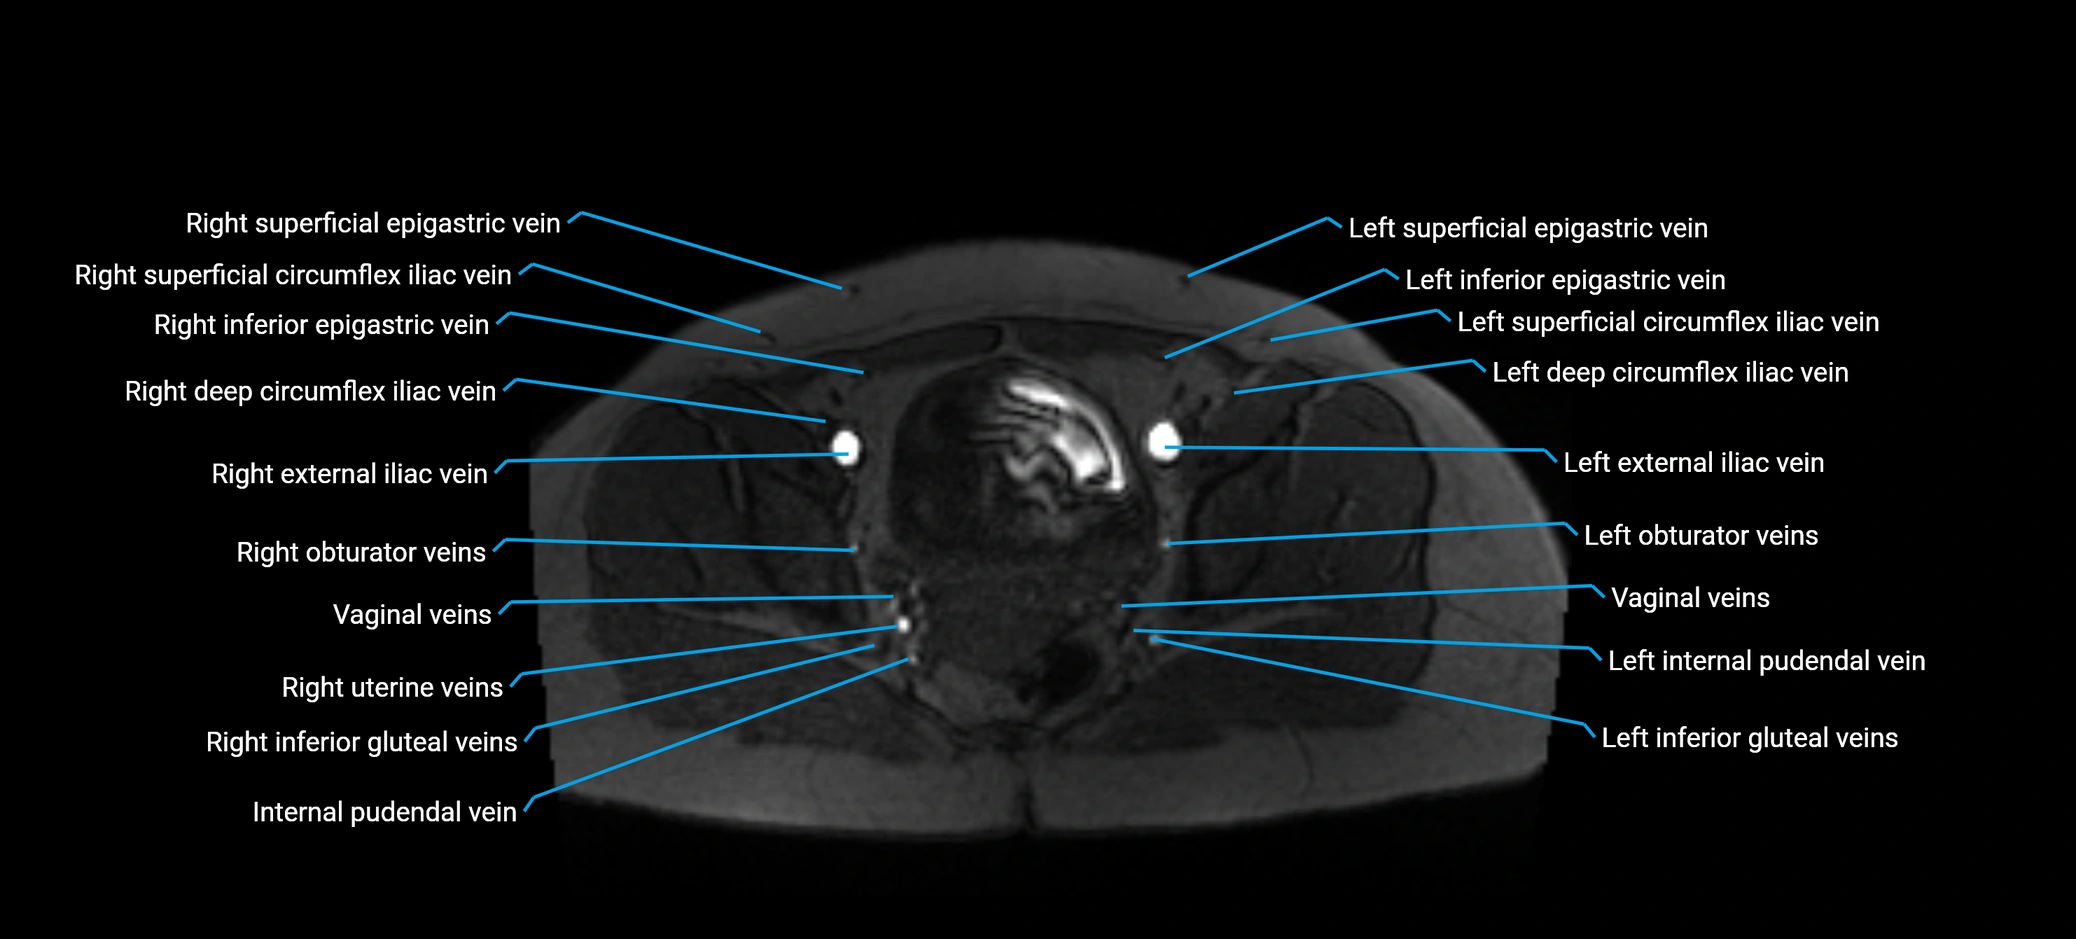

MRI image

image